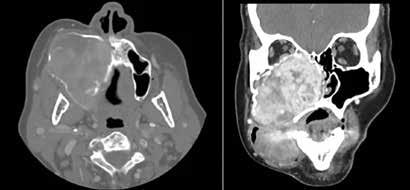

The diagnostic workup included computed tomography (CT) and magnetic resonance imaging (MRI), which clearly demonstrated the bilateral masses in the maxillary sinuses (figure 1). Because of the atypical bilateral presentation of the mucocele, we also performed electron microscopy to examine sinonasal mucosa tissue samples. This analysis revealed an absence of one of the microtubule doublets in three of the outer doublets of the axoneme (figure 2). To rule out etiologies such as cystic fibrosis and Kartagener syndrome, we obtained a chest x-ray and performed a chloride-in-sweat test; findings were normal. Our final diagnosis was isolated ciliary dysfunction.

Figure 1. A: Coronal CT shows the homogeneous isodense soft-tissue mass occupying both maxillary sinuses with bone remodeling of their walls, including the orbital floor. B: Axial T2-weighted MRI demonstrates the hyperintense cystic masses in both maxillary sinuses and the expansion of the orbital floor.